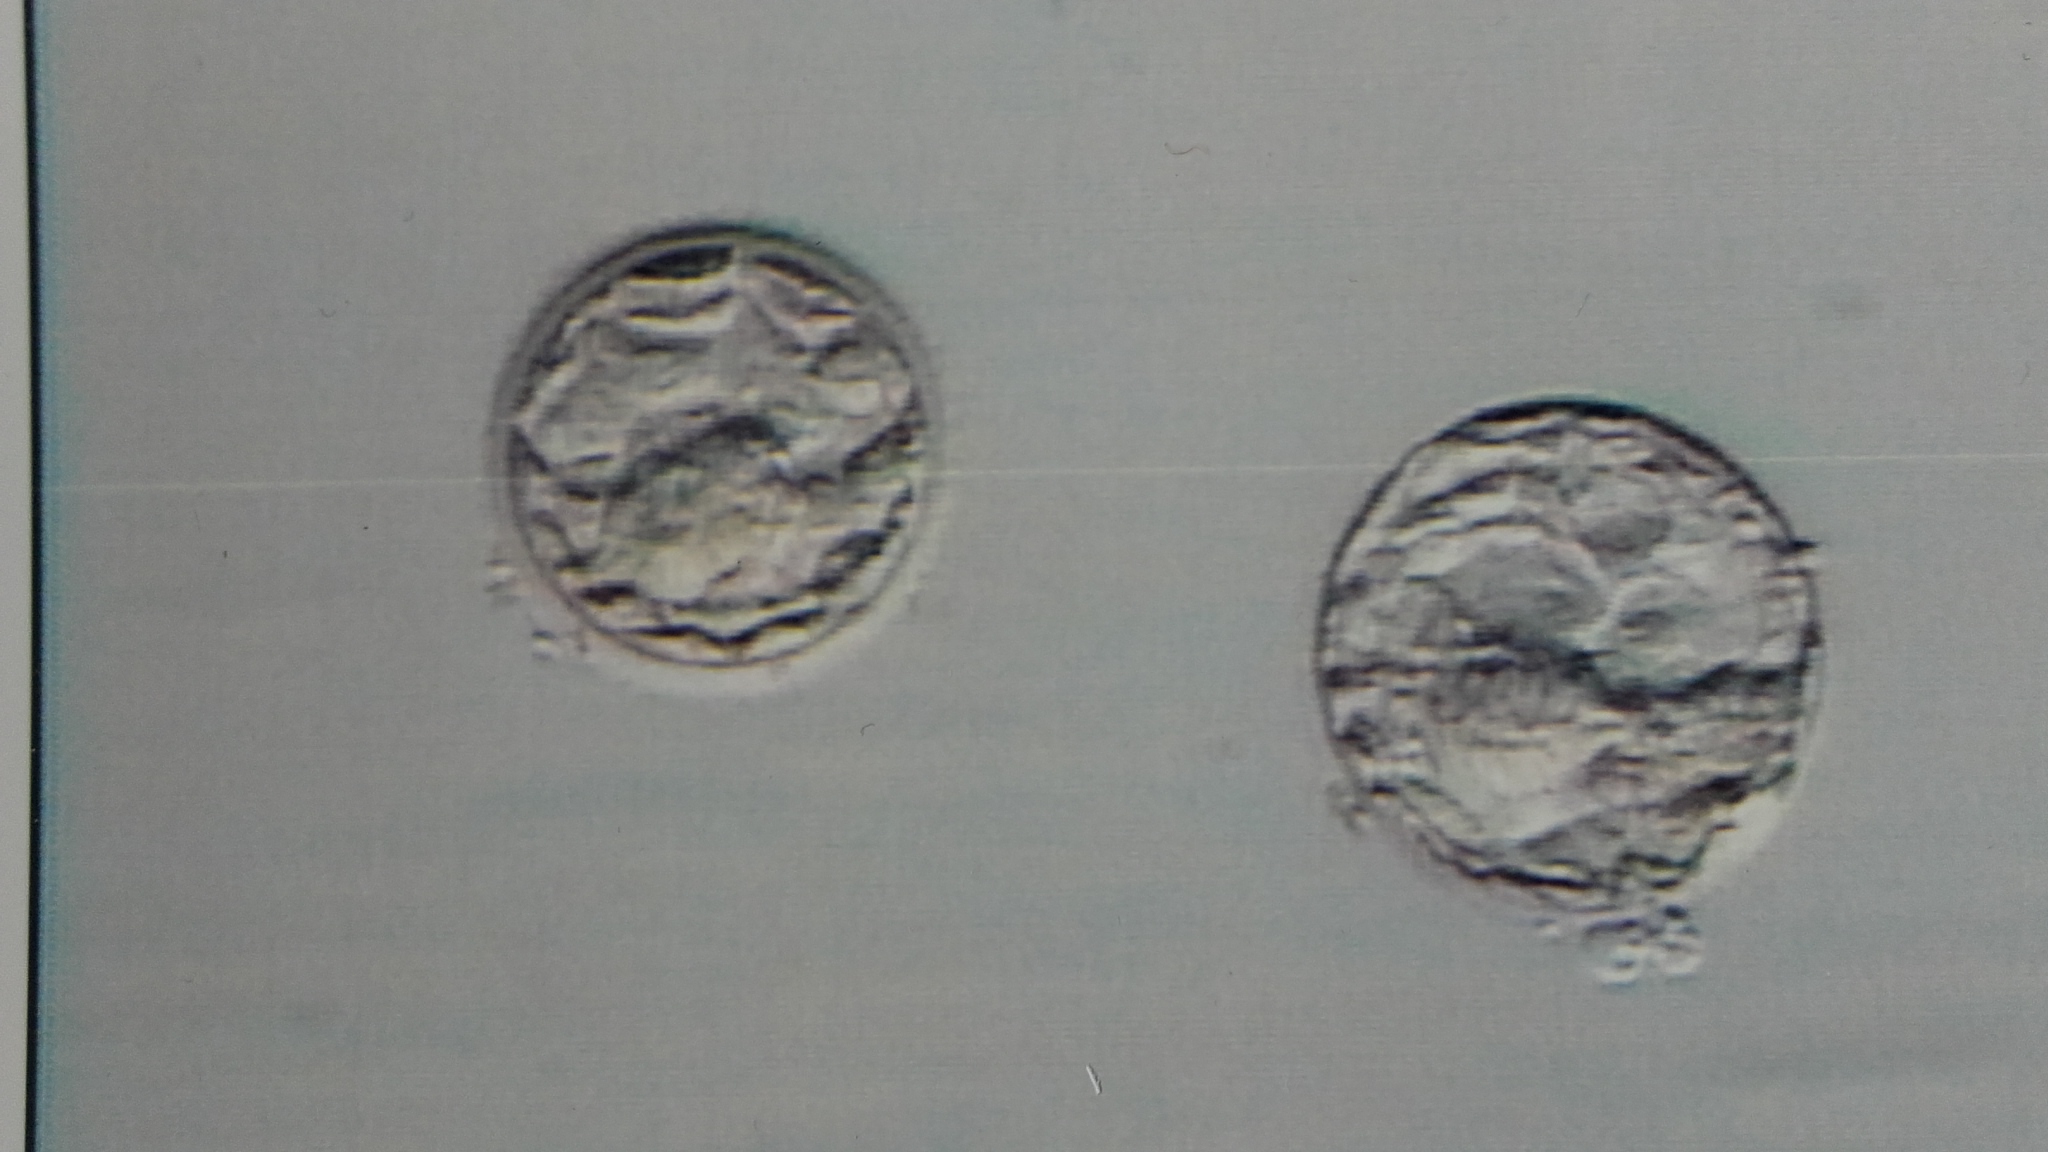

1. Wie bewerten sie die BCs? Mir wurde etwas von expandierten BCs gesagt (die eine eher expandierend, weil kleiner?). Die eine wohl schon beginnend, zu schlüpfen.

Umgekehrt. Die schlüpfende ist die rechte bzw. untere, wenn man das Bild öffnet. Das war aber gar nicht die Frage, oder? Die andere beginnt gerade erst zu expandieren, daher ist sie im Verhältnis deutlich kleiner und die Eihülle noch dicker. Die dünnt sich mit fortschreitender Expandierung dann immer weiter aus, bis sie dann so dünn ist, dass der Blastocyst durchbrechen und schlüpfen kann.

zwei schöne Tag5-BC: die kleiner Expandierungstufe 2 - 3, Score 3BB

die größere BC: Expandierungsgrad 3 - 4, Score 4BB. Als schlüpfende BC würde ich sie noch nicht bezeichnen.